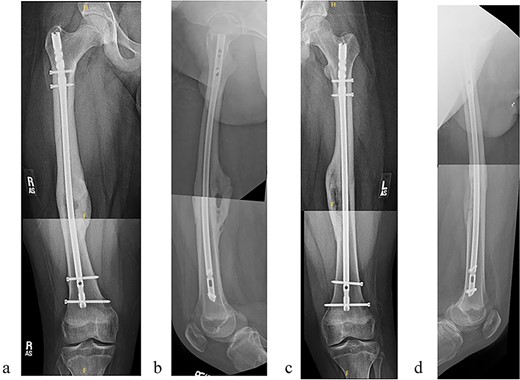

The patient tolerated the procedure well and recovered uneventfully. He was noted to have circumferential osseous healing at 1 year and underwent bilateral femur IMN removal 1.5 years postoperative without complication (Figs 4a–d and 5a–d).

(a) Right femur AP radiograph after implant removal. (b) Right femur lateral radiograph after implant removal. (c) Left femur AP radiograph after implant removal. (d) Left femur lateral radiograph after implant removal.